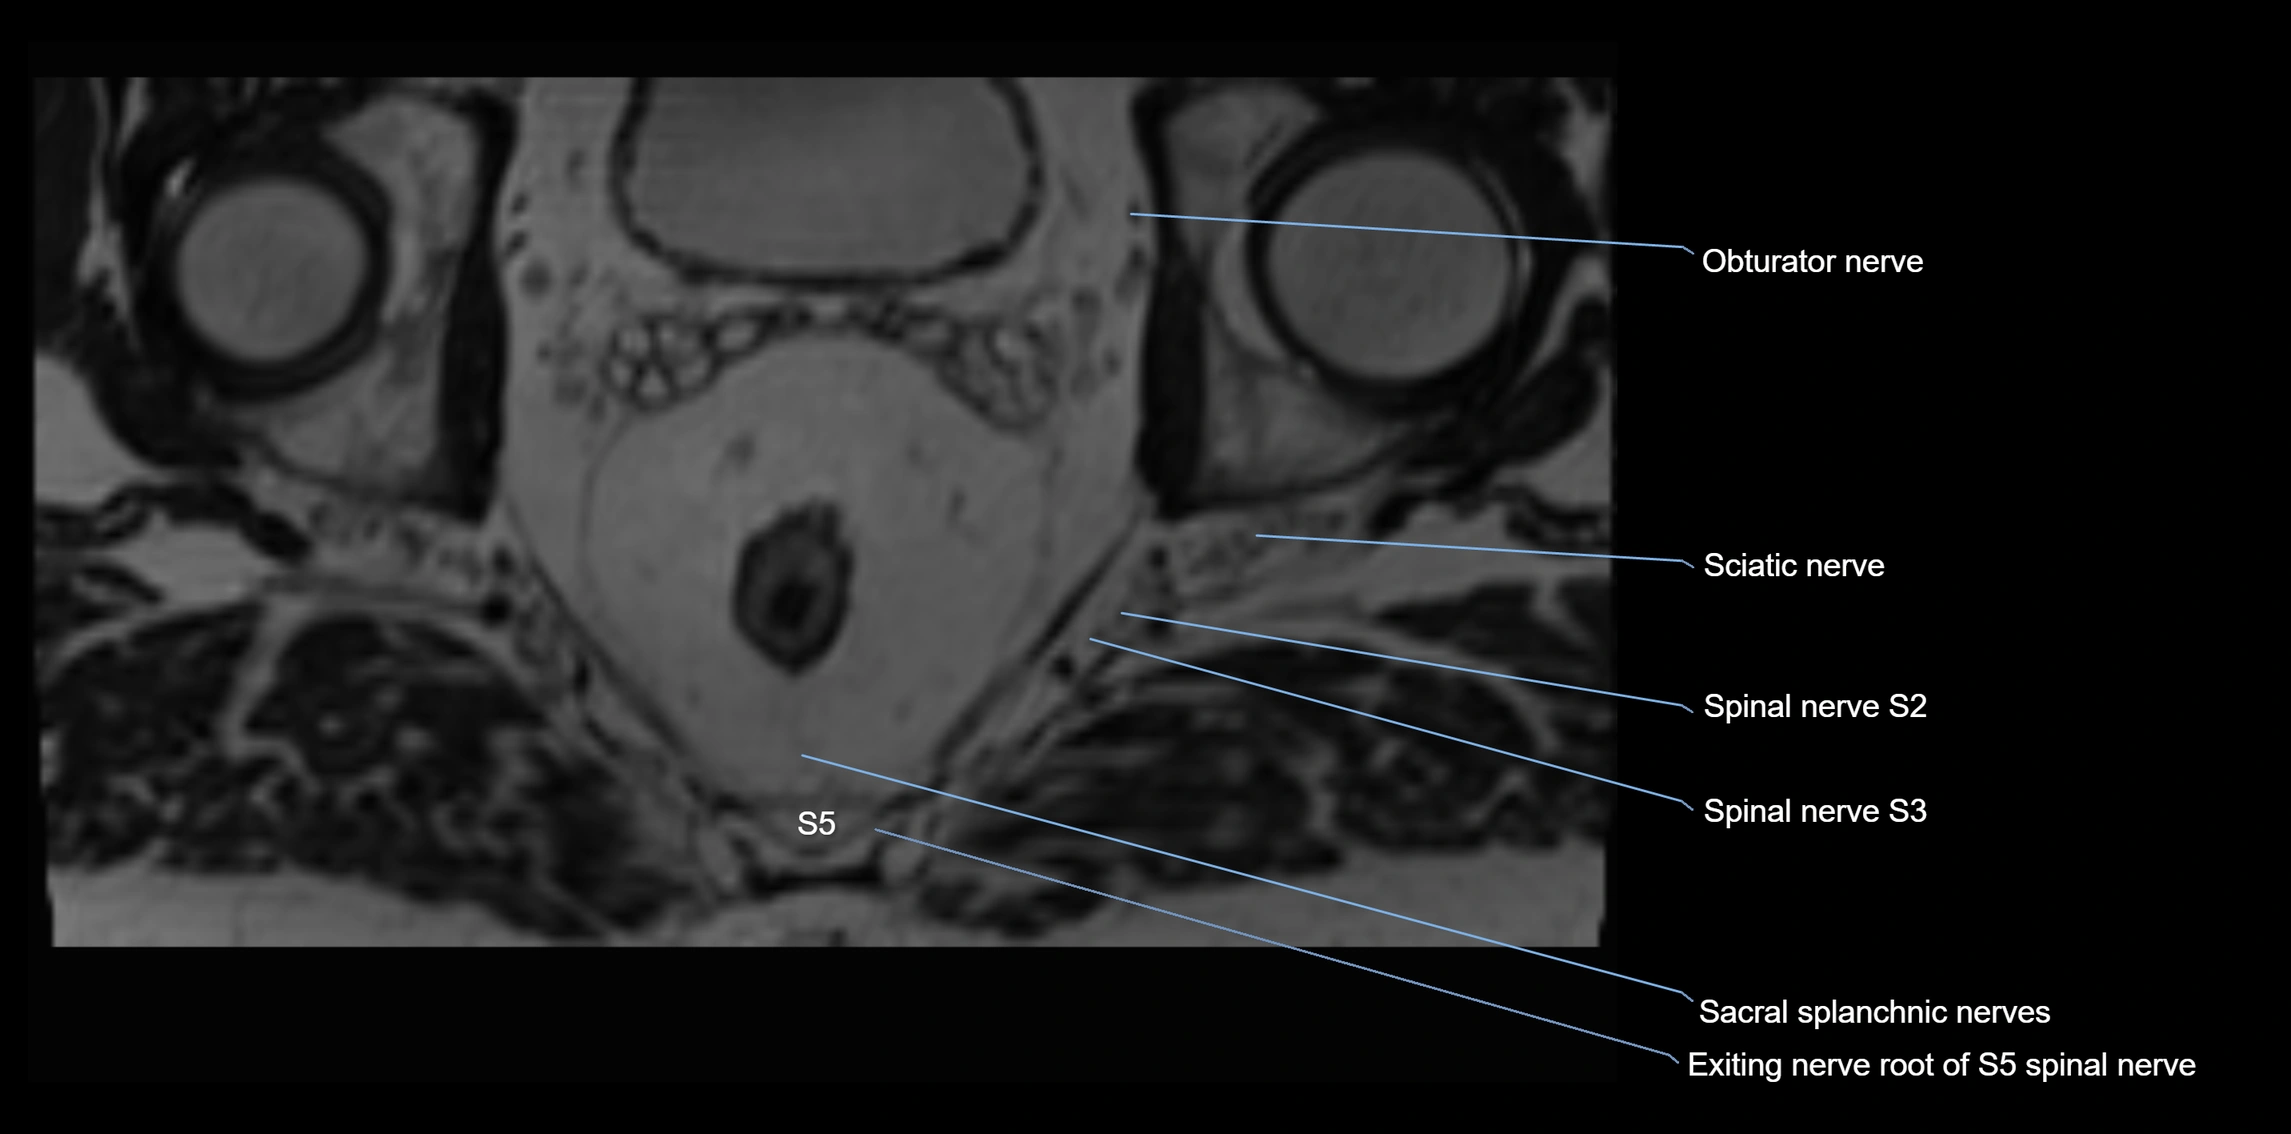

MRI Appearance

T1-weighted images:

• Nerve appears as a very thin low-to-intermediate signal intensity structure

• Surrounded by bright fat, aiding visualization

T2-weighted images:

• Nerve shows intermediate to mildly hyperintense signal compared to muscle

• Pathological involvement appears brighter

3D T2 SPACE / CISS:

• Nerve appears intermediate to mildly hyperintense compared to muscle

• Surrounded by bright fat or CSF, improving visualization

• Best sequence for mapping small pelvic nerves such as the anococcygeal

MRI image

image